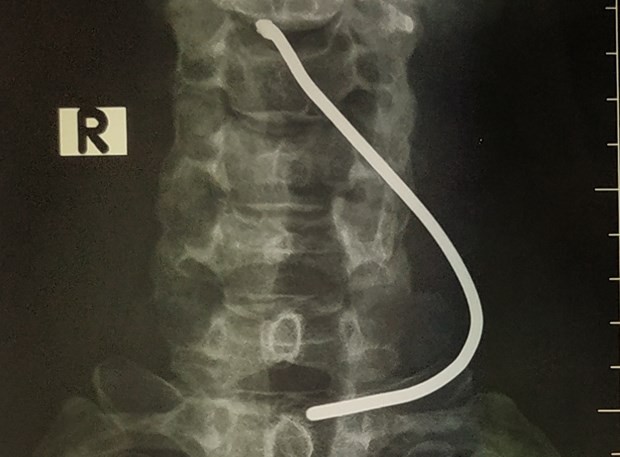

Hình ảnh chiếc thanh sắt cắm vào cổ bệnh nhân. (Ảnh: PV/Vietnam+).

Tin từ Bệnh viện Hữu nghị Việt Đức ngày 26/3 cho hay vừa tiếp nhận trường hợp người bệnh N.N.T (50 tuổi) sống tại Sơn Lôi (Vĩnh Phúc) nhập viện với tình trạng vùng cổ có vết thương gây ra bởi thanh sắt.

Người nhà bệnh nhân T. cho biết khi ông đang ngồi sửa xe máy ở trước cửa nhà thì có một ôtô tải đi qua. Chiếc xe bất ngờ nổ lốp tạo áp lực khiến  que sắt đang nằm trên đường bắn vào cổ bệnh nhân.

Người bệnh được chuyển lên bệnh viện đa khoa tỉnh trước khi chuyển Bệnh viện Hữu nghị Việt Đức vào 20 giờ ngày 24/3. Tình trạng của bệnh nhân khi ấy tỉnh táo, vùng cổ có vết thương thanh quản 0,5cm, tổn thương sụn giáp.

Thạc sỹ Dương Ngọc Thắng - Trung tâm Tim mạch và Lồng ngực (Bệnh viện Hữu nghị Việt Đức) đã tiến hành phẫu thuật thăm dò vết thương cho bệnh nhân T, lấy dị vật, khâu vết thương sụn giáp. May mắn cho bệnh nhân, thanh sắt xuyên qua sụn giáp, đi vào thanh quản nhưng không tổn thương dây thanh âm.

Sau mổ, sức khỏe của bệnh nhân T. ổn định và đã được xuất viện sau 3 ngày điều trị.